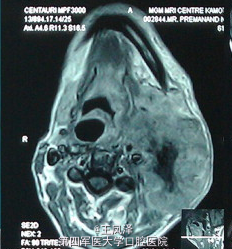

罕见颈部软组织肌上皮癌 1 例

患者男性,60 岁,颈部左侧无痛性占位病变 2 月,除肿胀增长速度较快外无任何明显不适症状。